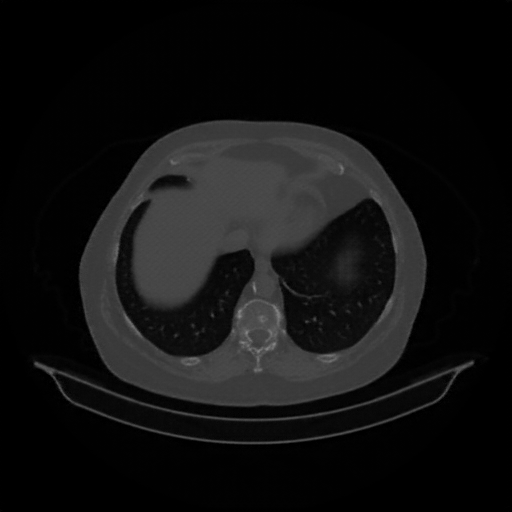

Image Grid

4Γ—3 grid: Rows show different image types (Original NATIVE, Reconstructed NATIVE, Original VENOUS, Generated VENOUS), Columns show windowing techniques (No Window, Lung Window, Mediastinum Window)

Original NATIVE CT scan (input)

Full window (WL 1023.5, WW 4095 β†’ Low βˆ’1024, High +3071)

Lung window (WL -600, WW 1500 β†’ Low βˆ’1350, High +150)

Mediastinum window (WL 40, WW 400 β†’ Low βˆ’160, High +240)